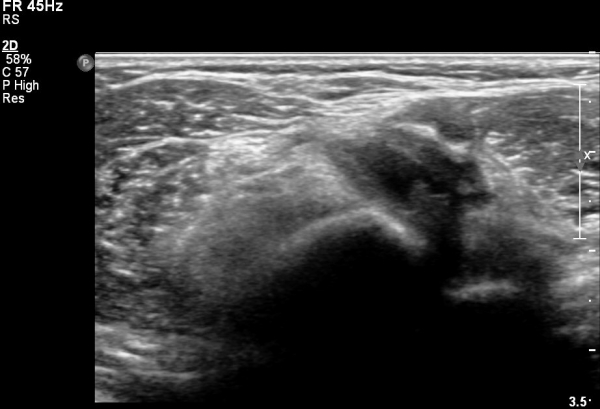

ŽÃËÀÚ¸¦ ¸»´ÜºÎ·Î À̵¿ÇÏ´Ï ¿ä°ñµ¶±â ÀÌµÎ¹Ú±Ù°Ç ÂøºÎ¿¡¼­ °ÏÀÌ Àú¿¡ÄÚ ºÎÁ¾ »óÅ·Π°üÂûµÇ°í(»çÁø 2)

Á¶±Ý´õ ¸»´ÜÀ¸·Î À̵¿ÇÏ´Ï °ÇÀÌ °üÂûµÇÁö ¾ÊÀ½(»çÁø 3).